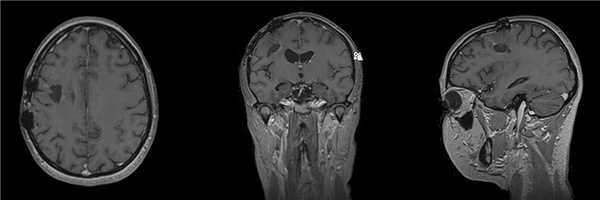

Пациентка 31 года, приступы утраты сознания с частотой около 2 раз в месяц беспокоят в течение 1,5 лет.

При МРТ выявлена опухоль левой височной доли с небольшим кистозным компонентом.

Пациентке проведена операция - микрохирургическое удаление внутримозговой опухоли левой височной доли

Гистологический диагноз - анапластическая плеоморфная ксантоастроцитома WHO grade III, BRAF-позитивная.

В послеоперационном периоде появления неврологического дефицита не отмечено.

При контрольной СКТ данных за остатки опухолевой ткани/ послеоперационные осложнения не получено.

Пациентка выписана на 7 сутки после операции.

В послеоперационном периоде проводилась лучевая, химиотерапия и таргетная терапия.